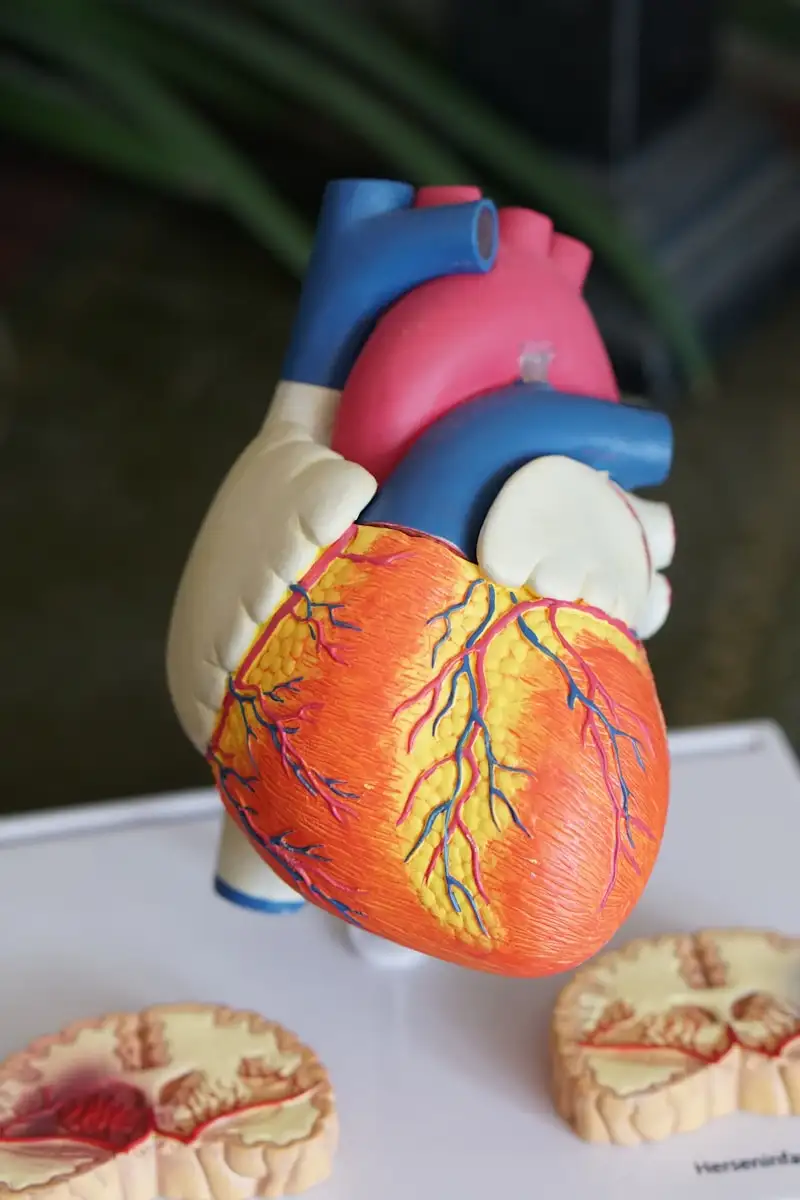

尼帕病毒之所以如此致命,在于它独特的入侵机制。与其他病毒不同,尼帕病毒使用一种几乎存在于所有哺乳动物细胞表面的分子作为它的"钥匙"——艾菲林B2和艾菲林B3受体。

艾菲林受体在人体中扮演着至关重要的角色:它们参与血管形成、神经细胞迁移和大脑发育。这些受体大量存在于血管内皮细胞、神经元和平滑肌细胞的表面。当尼帕病毒的糖蛋白G与艾菲林受体结合时,就像一把钥匙插进了锁孔,病毒的融合蛋白F随即启动,将病毒的外壳与细胞膜融合,将病毒RNA注入细胞内部。

2005年,这一发现被发表在《自然》杂志上,震惊了整个病毒学界。这意味着尼帕病毒具有极广的宿主范围——它能感染猪、马、狗、猫、人类,甚至实验中的豚鼠、仓鼠、雪貂和猴子。没有其他副黏液病毒拥有如此广泛的宿主谱。

更可怕的是,艾菲林受体在大脑中大量存在。当尼帕病毒进入人体后,它会沿着血液循环到达大脑,穿过血脑屏障,直接攻击神经元。这就是为什么尼帕病毒感染的主要表现是脑炎——大脑的严重炎症。

在显微镜下,尼帕病毒感染的大脑呈现出一种独特的模式。血管壁上出现炎症反应,形成血栓,导致周围脑组织缺氧坏死。这些微小的梗死灶散布在整个大脑皮层和脑干,就像无数颗微型炸弹在脑内爆炸。核磁共振成像显示,患者的大脑白质中布满了直径2至7毫米的高信号病灶——这些就是病毒留下的印记。